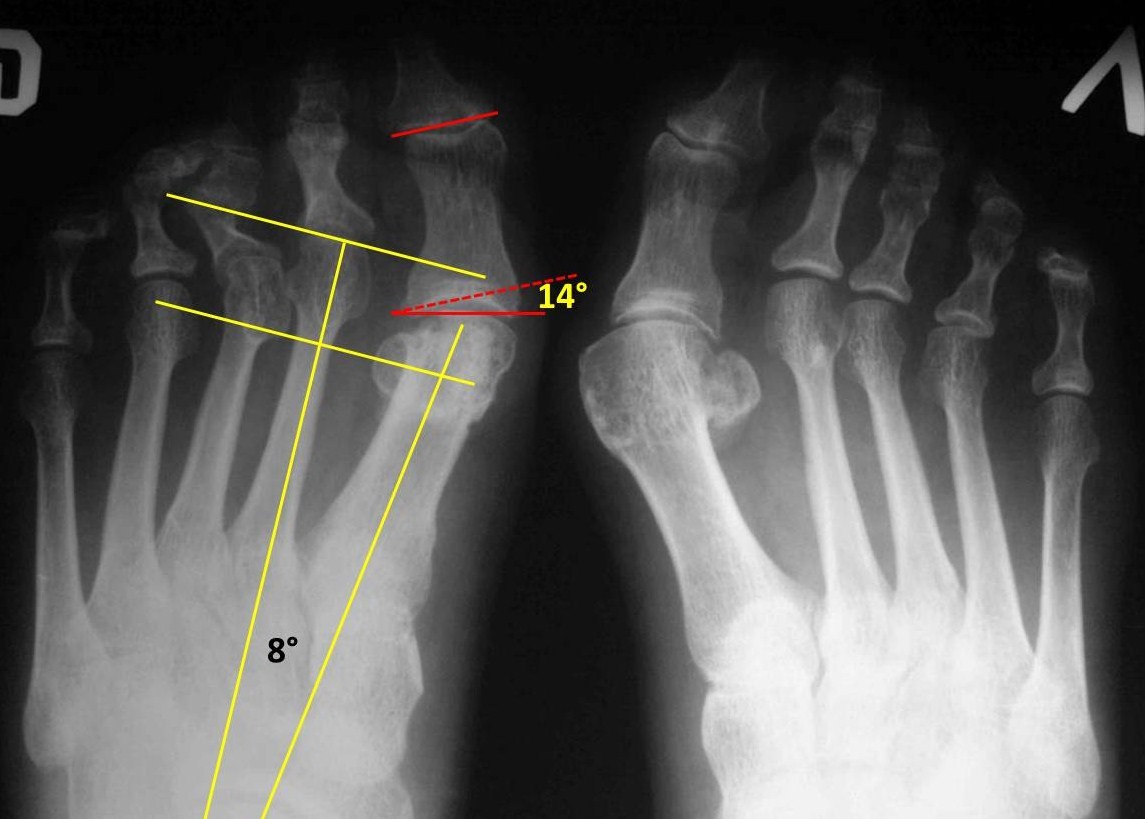

С первой плюсневой тут делать ничего не нужно, первый межплюсневый угол всего 8гр. (основные показатели отмечены схематично на рентгенограмме). Но имеется hallux valgus interphalangeus: угол между дистальной и проксимальной суставными площадками основной фаланги 14гр. Его лучше устранить с помощью остеотомии Akin, чтобы первый палец не мешал стать на место второму. Преобладание длин 2 и 3 плюсневых объясняет перегрузку их головок. 4-я плюсневая даже короче, чем могла бы быть относительно первой (перпендикуляр к оси 2 плюсневой, проведенный через середину латеральной сесамовидной кости, в норме должен пройти через середину головки 4 плюсневой. А он проходит выше). Получается, что вмешиваться нужно на 1 луче (дистальный Akin) и на втором с третьим. Задачи, которые тут нужно решить: укорочение 2 и 3 плюсневых (Weil, фиксированный или нет - на Ваш вкус) и устранение молоткообразной деформации 2-3 пальцев. Если она нефиксированная, то достаточным может оказаться подкожной тенотомии разгибателей на уровне плюснефаланговых суставов. Без всякой Z-пластики. А если деформация фиксированная или полуригидная, тогда на Ваш выбор: остеотомия основных фаланг или (хуже) резекция их оснований. Или еще что-нибудь.